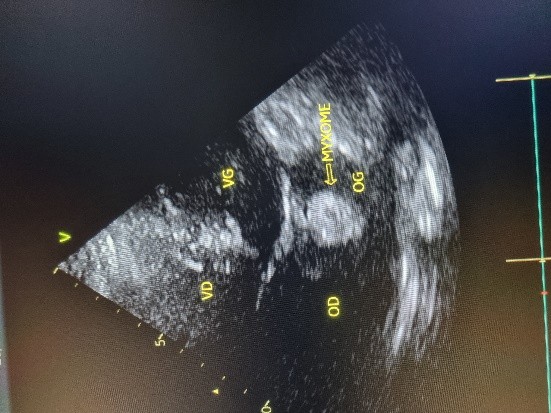

L’électrocardiogramme notait un rythme sinusal régulier avec une fréquence cardiaque à 83 bpm, des anomalies de la repolarisation en antéro septal à type d’ondes T biphasiques et en inférieur à type d’ondes T négatives asymétriques. La biologie était normale. L’échocardiographie (transthoracique et transœsophagienne) retrouvait les mêmes caractéristiques avec une masse appendue à la face atriale de la grande valve mitrale, obstruant partiellement l’orifice mitral et mesurant 49mm ×27 mm. Elle faisait protrusion dans le ventricule gauche en diastole (Figures 5 et 6). Cette masse était évocatrice d’un myxome de l’oreillette gauche. Le ventricule gauche n’était pas dilaté (DTDVG= 46mm), avec une fraction d’éjection systolique à 74% au Simpson biplan. Les pressions de remplissage du ventricule gauche étaient élevées. L’oreillette gauche était dilatée (VOG= 43mL/m²). Les cavités droites n’étaient pas dilatées. La fonction ventriculaire droite était normale (TAPSE= 24mm). On notait une hypertension pulmonaire avec PAPS =75mmHg, VmaxIT= 4,18 m/s. La veine cave inférieure était fine et compliante.

Figure 3 (a et b) : Echocardiographie transthoracique en mode bi dimensionnel montrant le myxome de l’oreillette gauche appendu au septum inter atrial vu en mode 4 cavités (a) et 2 cavités (b) chez un patient de 54 ans (Cas clinique n°2). VG= ventricule gauche; OG= oreillette gauche; OD= oreillette droite ; VD= ventricule droit.

Figure 4 (a et b): Echocardiographie transoesophagienne en bi dimensionnelle, incidence 4 cavités plan oblique à 135° montrant un myxome appendu au septum inter atrial (Cas clinique n°2). VG= ventricule gauche ; OG= oreillette gauche ; VD= ventricule droit.